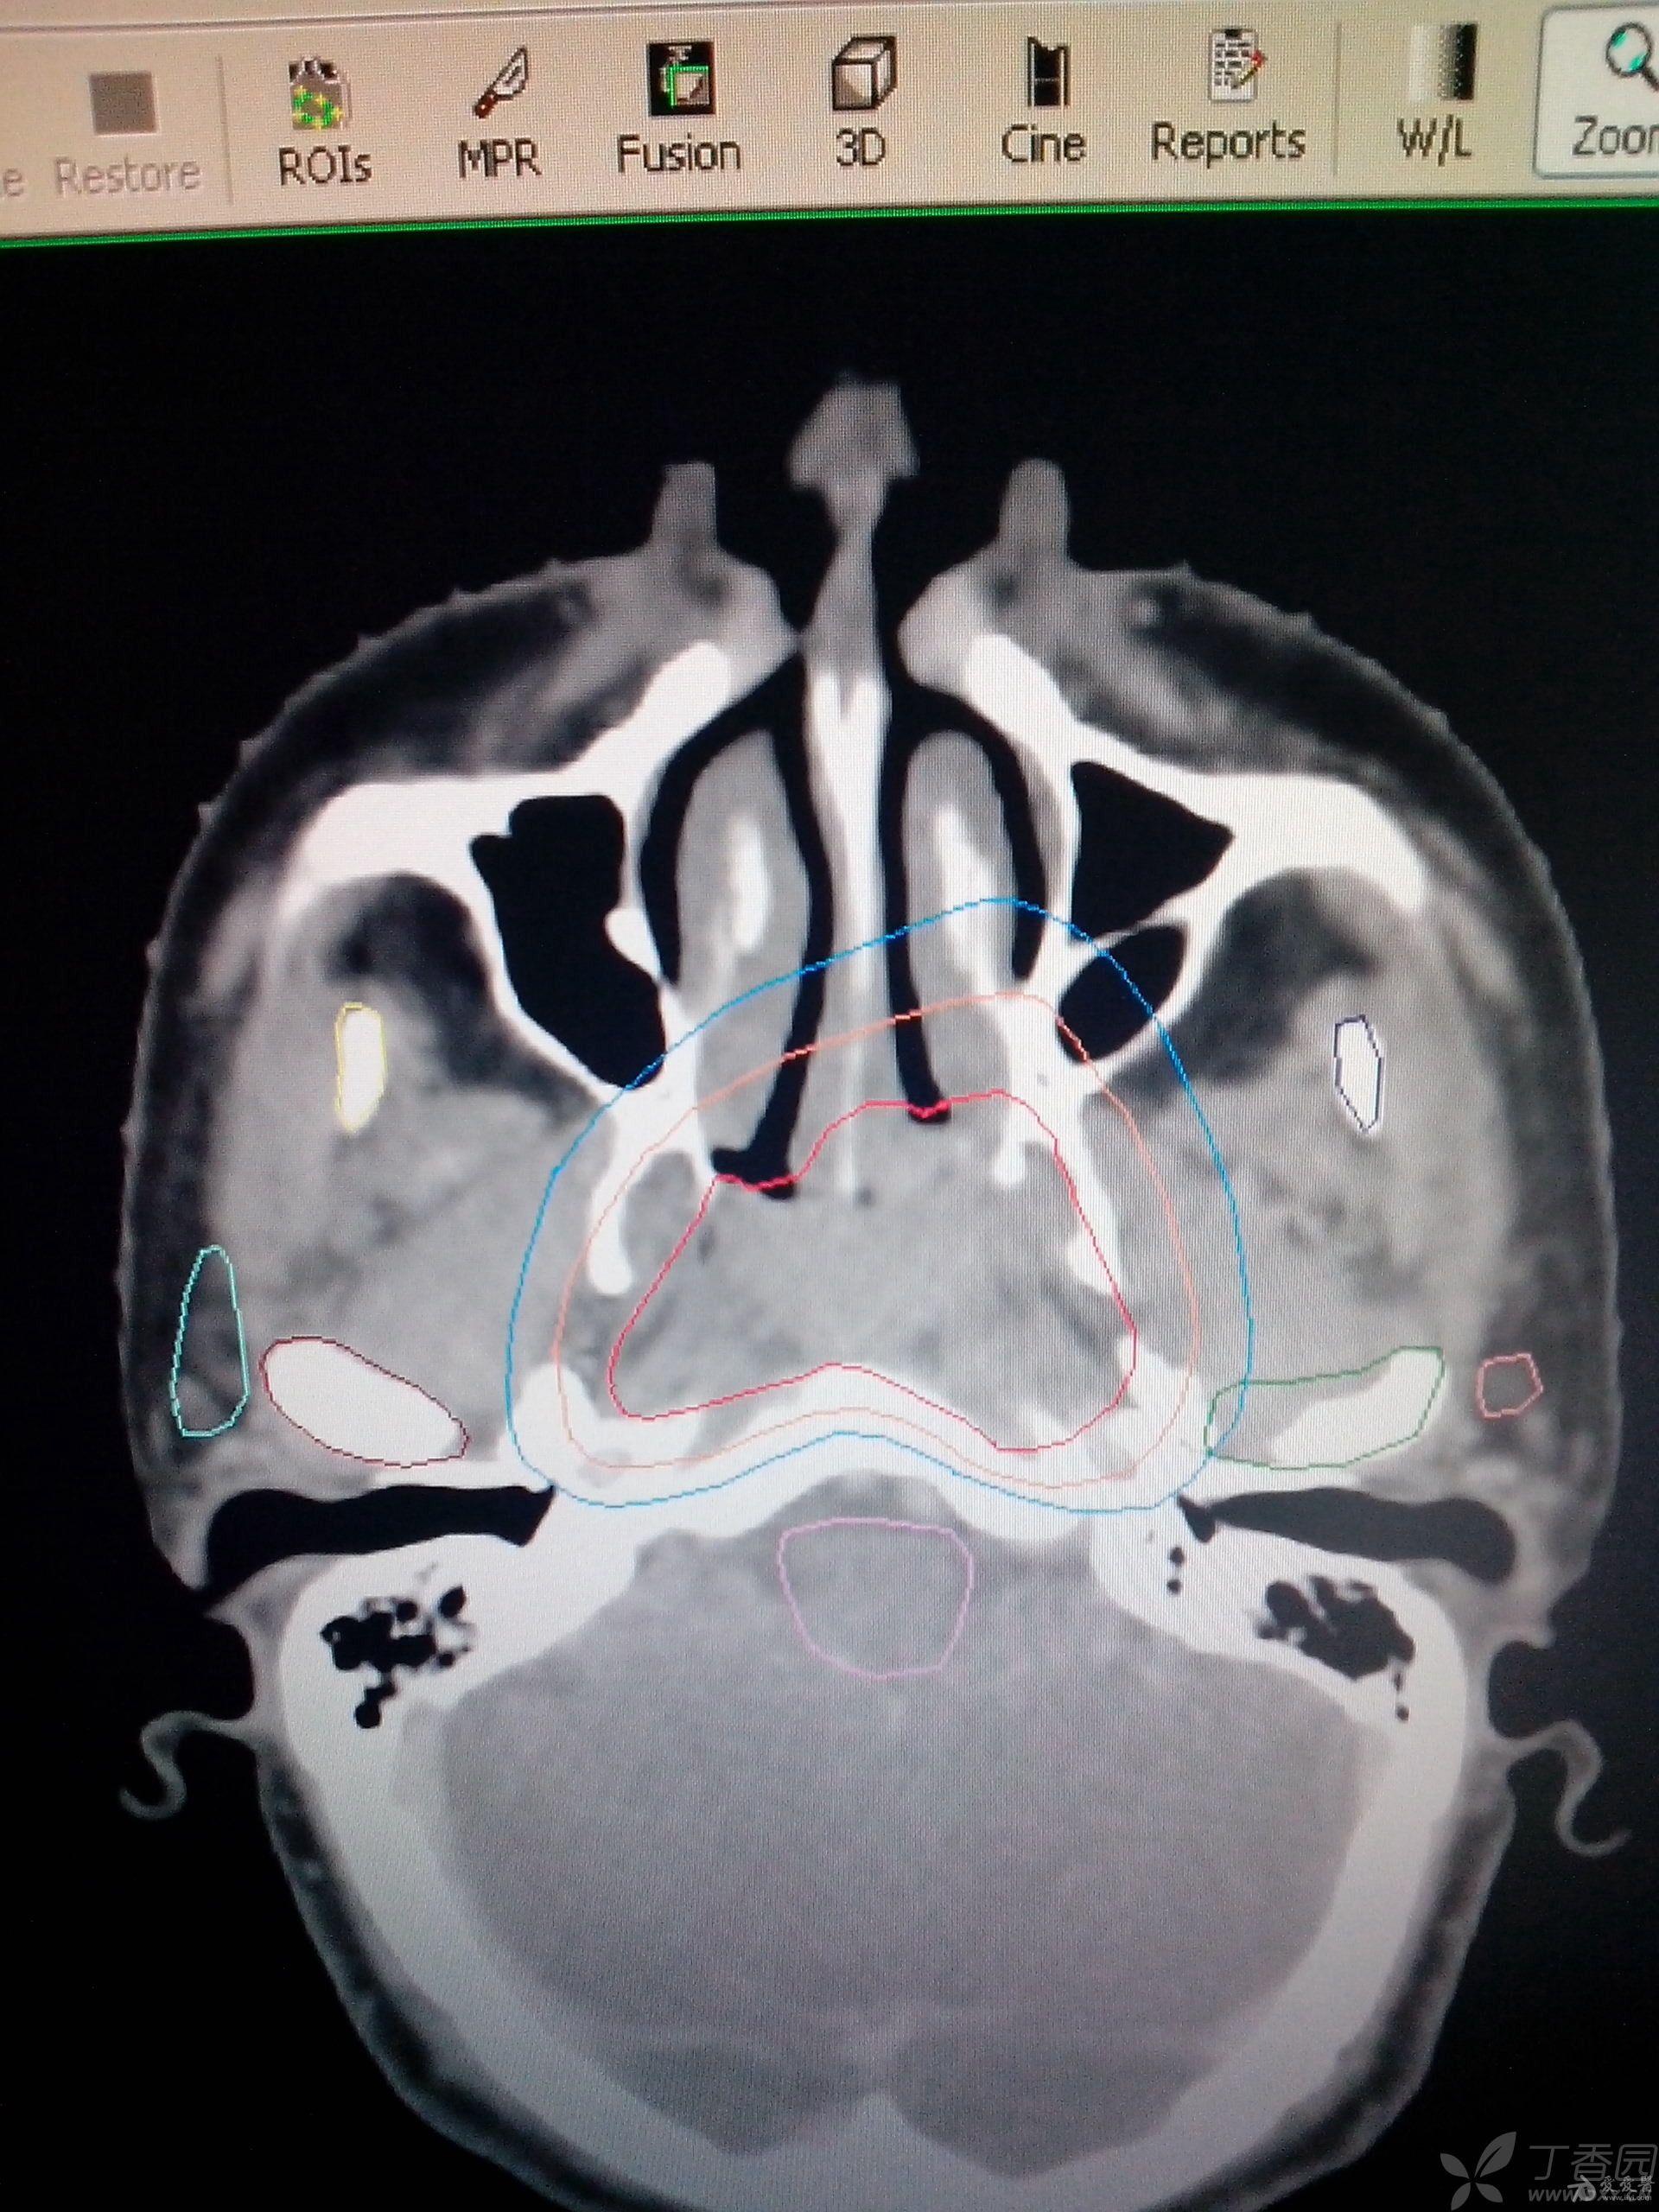

鼻咽癌靶区勾画的上界

图片尺寸1920x2560